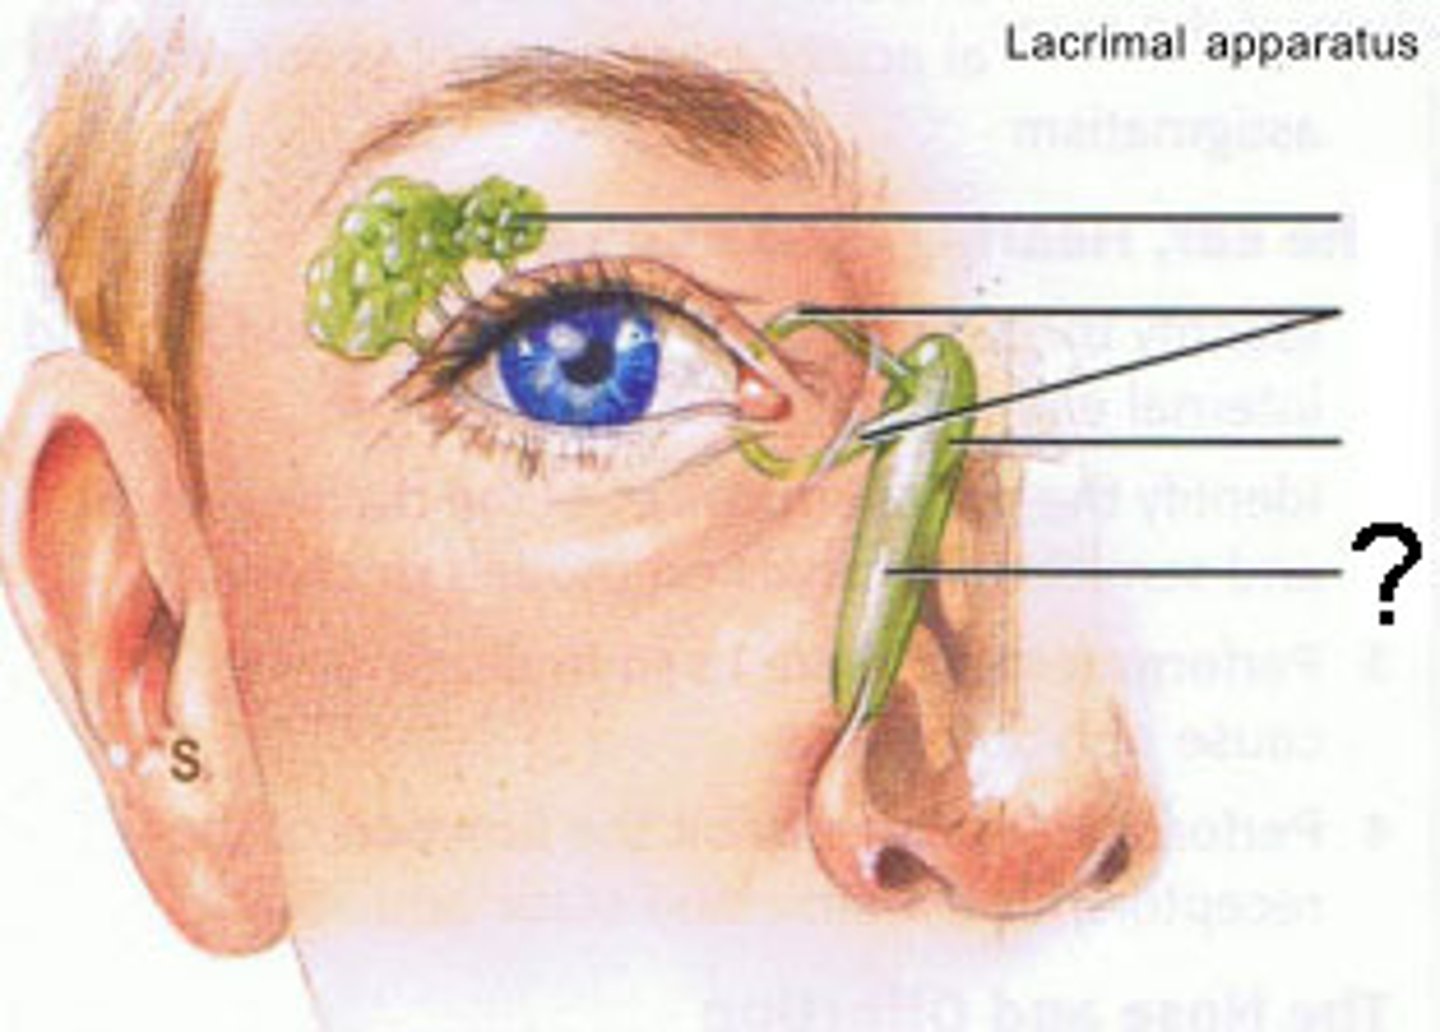

nasolacrimal duct

lacrimal gland